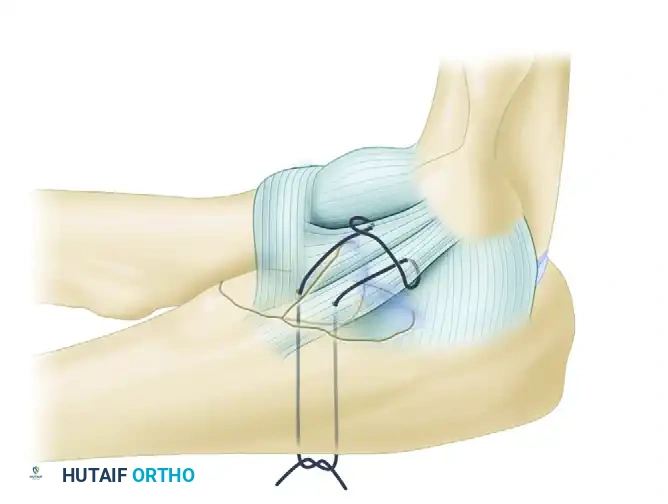

Small fragments cannot accept screws. Instead, they are reduced and fixed using heavy nonabsorbable sutures. The sutures are passed through the anterior capsule and the coronoid fragment, then shuttled through drill holes exiting the posterior aspect of the proximal ulna (olecranon). Tying these sutures posteriorly effectively anchors the anterior capsule and coronoid tip back to their anatomic bed, restoring the anterior soft-tissue buttress.

FIGURE 57-62 A: Small coronoid fracture fragments and the attached anterior capsule can be securely fixed with transosseous sutures passed through the proximal ulna.

FIGURE 57-67 B: The anterior capsule is captured by nonabsorbable sutures and secured through drill holes in the fracture bed of the coronoid.